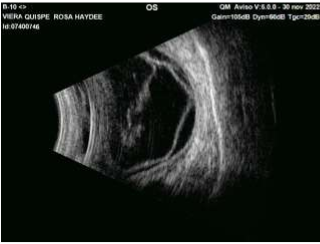

Tomografía de coherencia óptica de segmento anterior, glaucoma y macula, angiografía ocular,  topografía corneal, campos visuales computarizados, ecografía ocular, biometría, microscopia especular.